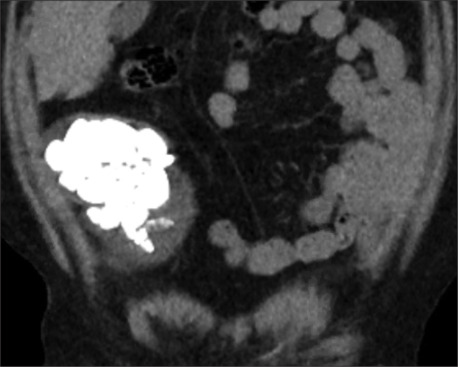

Results: Seven patients underwent a total of nine PCCLs between 2019 and 2023. Sone burden ranged from 4 to 10 cm. No intraoperative complications were faced. Three patients had residual stone fragments < 7 mm in size. Suprapubic catheter was removed between days 0 and 3 postoperative. Cystostomy was left to close spontaneously, none of the patients developed peritoneal leak after removal. Patients with Mitrofanoff channel reported no leak or compromise to the continued mechanism. Predominant stone composition was magnesium ammonium phosphate (struvite) in seven cases.

Abstract Image